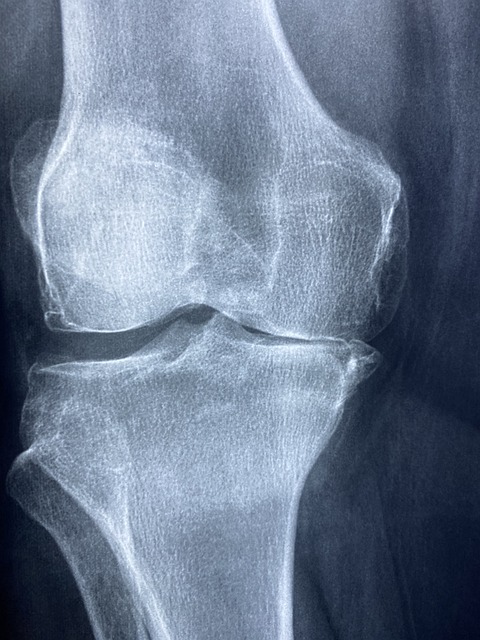

콘드로이친은 그리스어로 chondros, “연골”이란 뜻으로, 관절과 연골을 구성하는 주요 성분 중 하나다. 관절은 뼈와 뼈 사이를 연결해주어 우리의 움직임이 가능하게하고, 연골은 관절과 관절 사이에 위치하여 충격을 흡수하고, 뼈가 부드게 움직일 수 있도록 한다. 관절과 연골의 주요 구성성분으로는 글루코사민, 콘드로이친, 콜라겐 등이 있다. 그러나 나이가 들수록 이 성분들이 감소하여 관절의 불편함을 많이 겪게 되는데. 글루코사민과 콘드로이친 모두 나이가 들수록 빠르게 감소하기 때문에 외부로부터 꾸준히 보충해주어 관절 건강을 챙겨주는 것이 중요하다

연골은 관절마다 뼈를 보호하는 물질이며 관절이 불편함 없이 움직이는데 도움을 준다. 많은 운동선수들은 운동중 부상으로 연골을 다치거나 제거하기도 하며, 나이가 들면서 자연스럽게 줄어들기도 한다. 보통 관절이 아프게 되면, 관절염을 의심하는데 이는 연골이 닳아 관절이 뻣뻣하고 유연성이 떨어지면서 통증이 생기게 된다. 콘드로이친이 제공하는 효과중에 가장 으뜸으로는 관절염의 주 원인으로 알려져있는 연골을 보호하고 예방해준다.

관절 속 충격완화 및 충격을 방지하는 역할을 하는 콘드로이친 성분으로 하여금 연골 형태 및 탄력을 유지시킴으로 통증은 완화시키고 염증은 억제할 수 있다. 연구 결과 통증 완화 감소 정도가 소염진통제 만큼 뛰어나다고 밝혔다.

관절염에 대한 보충제를 연구하는 기관중 하나인 GAIT에서는 1,500명 이상의 관절염 환자들에게 글루코사민과 콘드로이친을 처방하여 조사한 결과에를 보면, 콘드로이친을 복용한 그룹이 무릎 관절에 붓기가 개선 되었다는 연구 결과를 밝혔다. 이를 바탕으로 콘드로이친은 무릎 염증과 붑기 완화에 도움을 줄 수 있다.